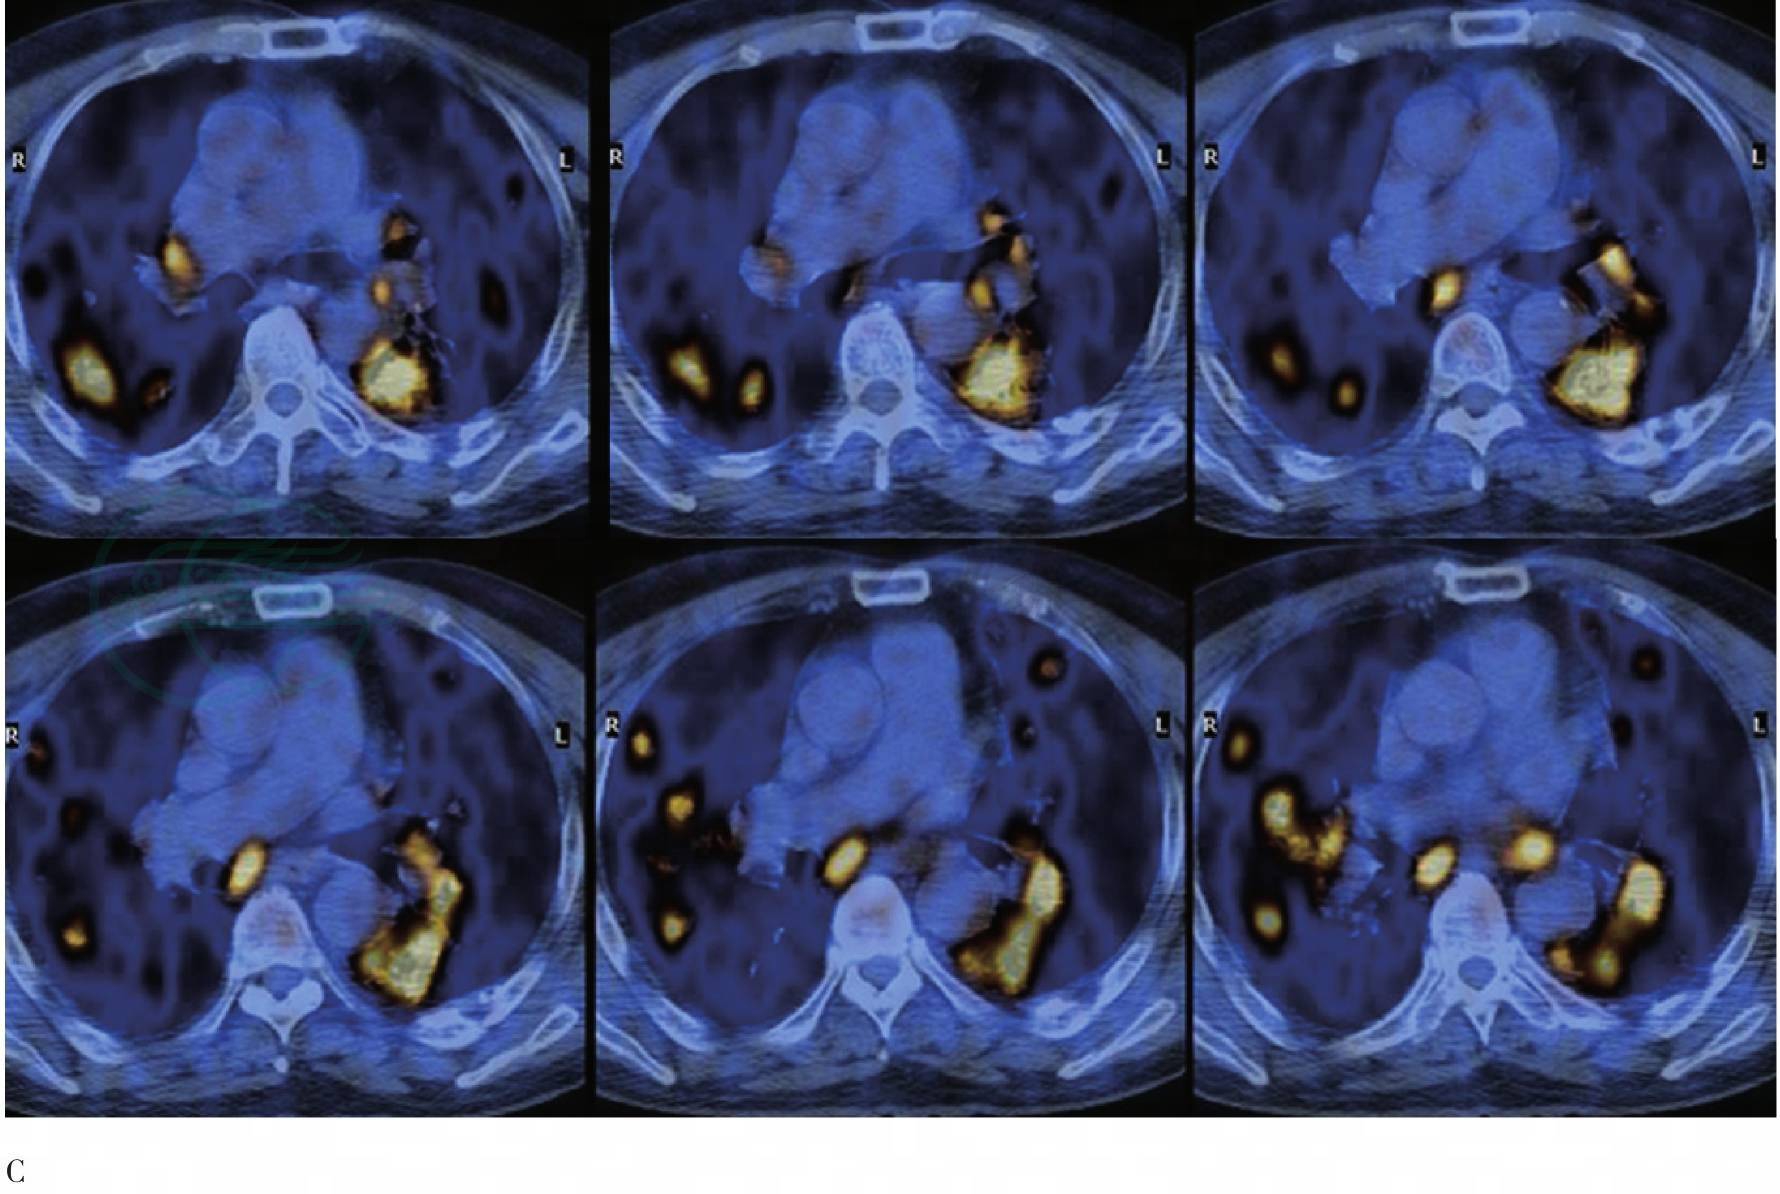

图2 治疗前PET/CT胸部横断层图

A. CT肺窗;B. CT纵隔窗;C. PET/CT融合图像。双肺肺野内多发大小不一、形态各异的密度增高影,边缘模糊,密度不均匀,部分病灶FDG代谢增高;纵隔及双侧肺门多个肿大淋巴结,FDG代谢增高